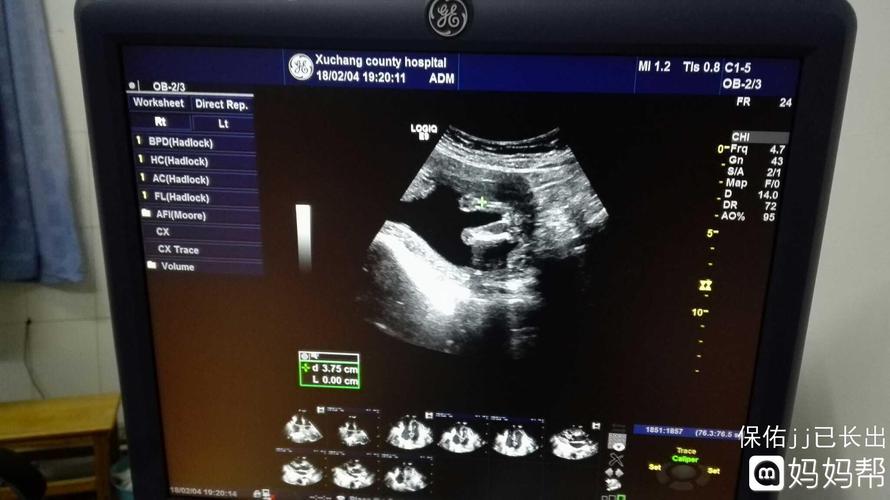

怀女孩彩超图,四维单子上蓝色是男孩

今天的彩超女宝图最后一张是三条线的

听说四维彩超能看出男孩女孩?朋友说我的是女孩不知道准不准!

今天去照了四维彩超,找熟了看了是女孩,第一胎也是女宝,虽然不讨厌

怀女孩彩超图三条线

女孩彩超图片

怀女孩的彩超单图片

怀女孩彩超图片特点